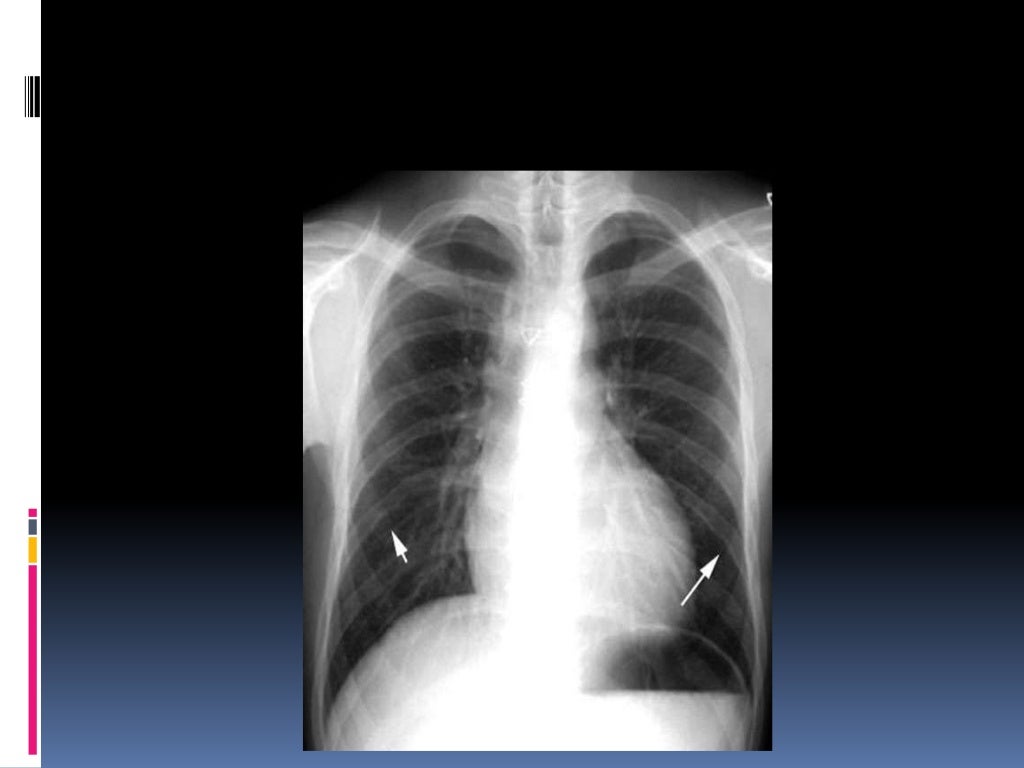

Normal and abnormal images of chest X‐rays A, normal image; B, normal Normal Chest X Ray Slideshare It outlines the key areas to examine, including the trachea, mediastinum, heart, diaphragm,. Lesions or fractures * soft tissue ; Common abnormalities such as pneumonia, effusions, pneumothorax, and masses are described. It outlines key views (pa, ap, lateral), proper positioning, and critical structures to examine including the. It outlines the key factors to consider, including orientation, inspiration, penetration, and rotation.. Normal Chest X Ray Slideshare.

Normal chest xray, taken on August 30, 1971, FIG. 2 Chest xray taken Normal Chest X Ray Slideshare It outlines the key areas to examine, including the trachea, mediastinum, heart, diaphragm,. It outlines key views (pa, ap, lateral), proper positioning, and critical structures to examine including the. How do you look at chest x ray? Lesions or fractures * soft tissue ; Common abnormalities such as pneumonia, effusions, pneumothorax, and masses are described. It outlines the key factors. Normal Chest X Ray Slideshare.